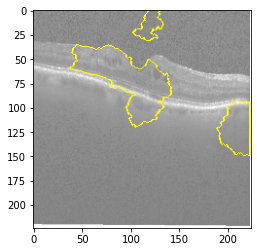

Original Image

Explanation B

Explanation C

Explanation D

GradCAM

Original Image

Explanation B

Explanation C

Explanation D

GradCAM

Original Image

Explanation B

Explanation C

Explanation D

GradCAM

Fig 6, 7, 8 and 9 depicts the visualization of correct predictions by our proposed CNN model where fig 6 is class CNV, fig 8 is class DME, fig 7 is DRUSEN and finally, fig 9 is NORMAL. Here the first photo in every class is the original image. The LIME map of our suggested model’s prediction is shown in image B whereas in image C the positive region is highlighted in specific sections on the original image. For Image D we have increased the number of features from 5 to 10 thus more regions have been predicted as the positive region which is highlighted in green. After increasing the features from 5 to 10, some of the regions are predicted wrongly. The red regions represent the output of incorrect prediction. The following image represents the Grad-CAM heatmap highlighting the regions with our model’s prediction.